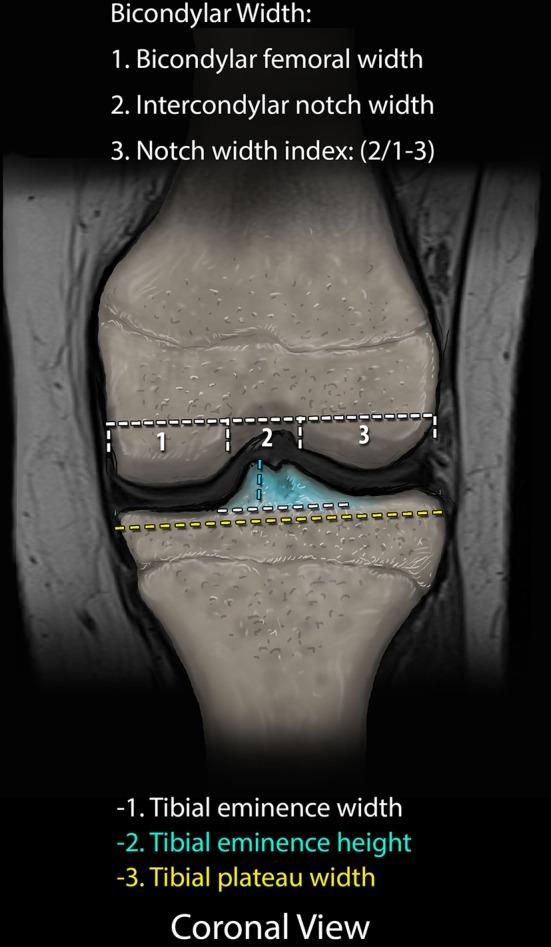

A retrospective review of pediatric patients undergoing knee magnetic resonance imaging (MRI) was performed over a 4-year period. Inclusionary criteria included mid-substance ACL disruption, skeletal immaturity, noncontact injury, without associated ligamentous disruption, and no medical condition associated with ligamentous laxity. MRI studies were analyzed by a pediatric musculoskeletal radiologist, measuring identified bony parameters, and compared with an age-matched control group without ligamentous injury. Data were analyzed using unpaired t-tests and logistic regression.

对4年间接受膝关节磁共振成像(MRI)检查的儿科患者进行回顾性研究。纳入标准包括ACL实质中部断裂、骨骼未成熟、非接触性损伤、无相关韧带断裂,且无与韧带松弛相关的疾病。MRI研究由儿科肌肉骨骼放射科医生进行分析,测量已识别的骨骼参数,并与无韧带损伤的年龄匹配对照组进行比较。数据采用非配对t检验和逻辑回归分析。